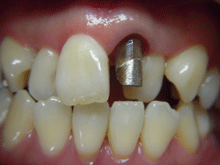

セ ラ ミ ッ ク ク ラ ウ ン

内面には金属を使用し、外面にセラミックを築成するタイプで、従来多くがこの方法で治療されていました。

症 例